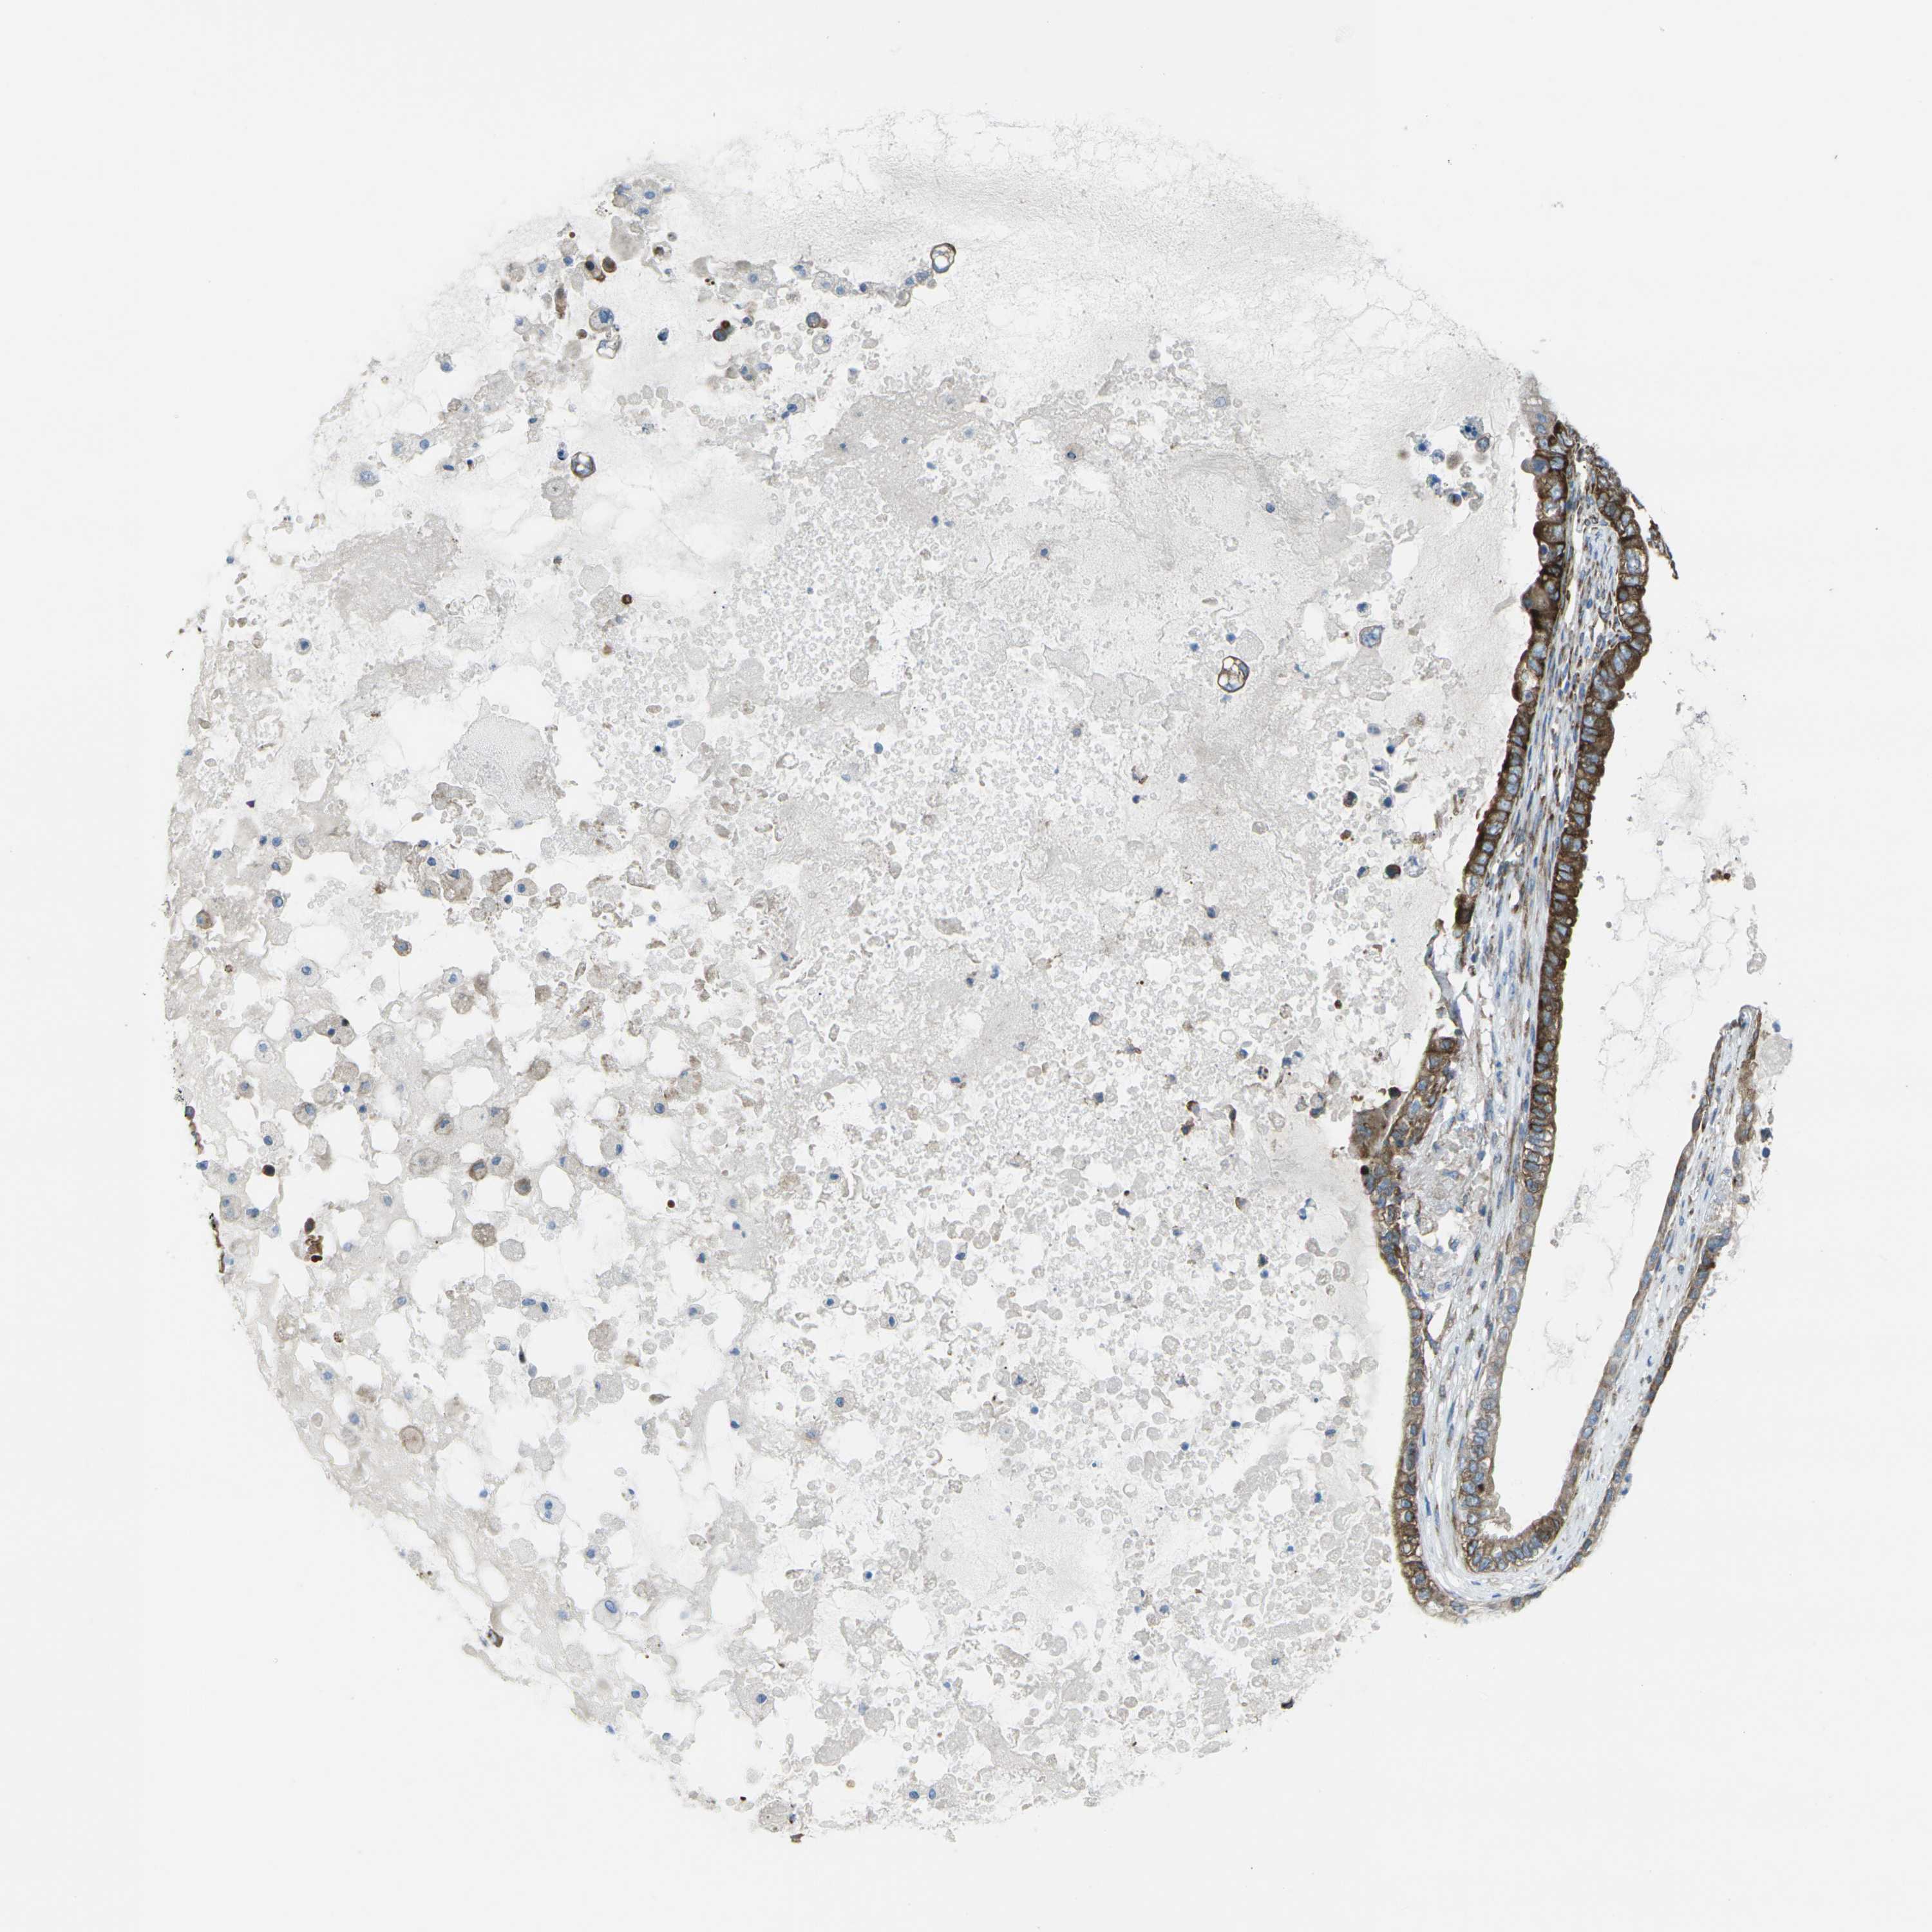

OVARIAN CANCER - Protein expressioni

A mouse-over function shows sample information and annotation data. Click on an image to view it in a full screen mode. Samples can be filtered based on level of antibody staining by selecting one or several of the following categories: high, medium, low and not detected. The assay and annotation is described here.

Note that samples used for immunohistochemistry by the Human Protein Atlas do not correspond to samples in the TCGA dataset.

Antibody stainingi

Antibody staining in the annotated cell types in the current human tissue is reported as not detected, low, medium, or high, based on conventional immunohistochemistry profiling in selected tissues. This score is based on the combination of the staining intensity and fraction of stained cells.

Each image is clickable and will lead to virtual microscopy that enables deeper exploration of all samples and also displays staining intensity scores, fraction scores and subcellular localization as well as patient and tissue information for each sample.

Antibody HPA013952

Staining

High

Medium

Low

Not detected

Intensity

Strong

Moderate

Weak

Negative

Quantity

>75%

75%-25%

<25%

None

Location

Nuclear

Cytoplasmic/membranous

Cytoplasmic/membranous,nuclear

Cystadenocarcinoma, serous, NOS

Carcinoma, endometroid

Cystadenocarcinoma, mucinous, NOS

Carcinoma, NOS